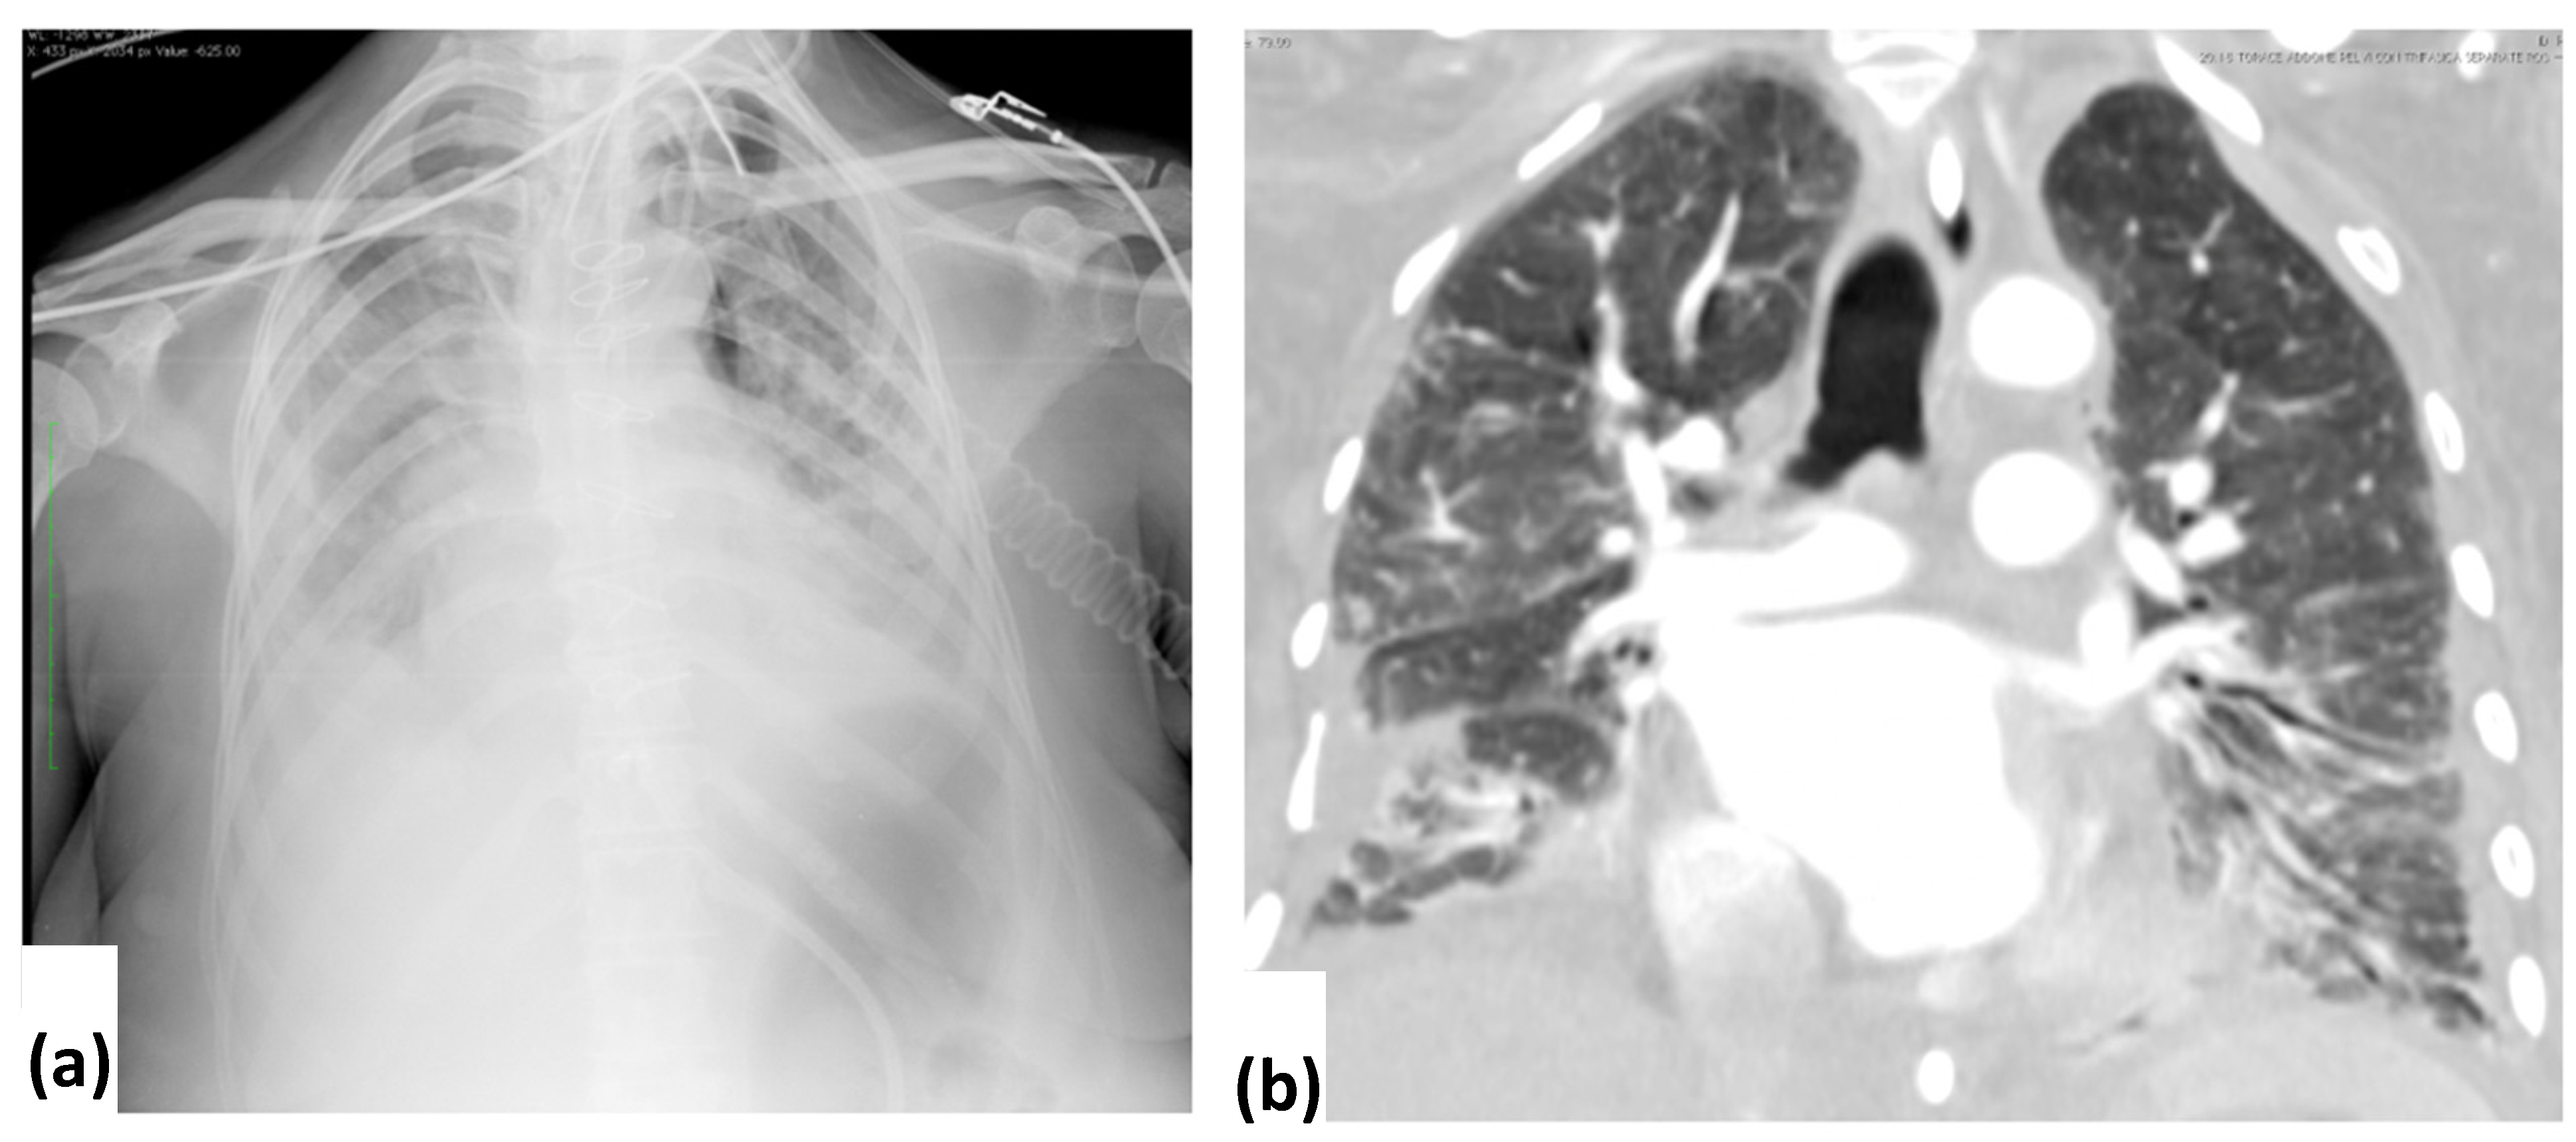

3.2. CXR Findings and Disease Distribution

3.3. CT Findings and Disease Distribution